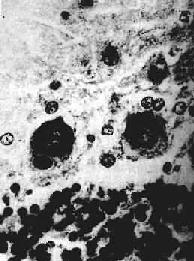

图16-16 流行性乙型脑炎 脑组织内有多发性镂空软化灶 4)胶质细胞增生小胶质细胞增生明显,形成小胶质细胞结节(图16-14),后者多位于小血管或坏死的神经细胞附近。少突胶质细胞的增生也很明显。星形胶质细胞增生和胶质瘢痕形成,在亚急性或慢性病例中较为多见。 【临床病理联系】 本病病变分布广泛,神经细胞广泛受累,患者常出现嗜睡、昏迷以及颅神经核受损所致的颅神经麻痹症状。由于脑内血管扩张充血,血流淤滞、血管内皮细胞受损,致血管通透性增高而引起脑水肿和颅内压升高,病人常出现头痛、呕吐。严重的颅内压增高可引起脑疝,其中小脑扁桃体疝可致延髓呼吸中枢受压而致死。由于脑膜有不同程度的反应性炎症,临床上有脑膜刺激症状和脑脊液中细胞数增多的现象。 本病患者经过治疗,大多数在急性期后可痊愈,脑部病变逐渐消失。病变较重者,可出现痴呆、语言障碍、肢体瘫痪及颅神经麻痹引起的吞咽困难、中枢神经性面瘫、眼球运动障碍等,这此表现经数月之后多能恢复正常。少数病例病变不能完全恢复而留下后遗症。 (四)狂犬病 狂犬病(rabies)是狂犬病毒引起的传染病。狂犬病的流行于犬、猫等(狼、蝙蝠等亦可感染),成为狂犬病毒的贮存宿主。人被病犬(或病猫等)咬伤,唾液中的病毒经伤口侵入人体,沿周围神经(主要是感觉神经)至背根节经脊髓入脑而致病。 狂犬病的潜伏期随伤口的部位而异,如面部咬伤者潜伏期较下肢被咬伤者要短得多。本病临床表现为创口疼痛、头痛、发热、不安、怕风,饮水时反射性咽喉痉挛,故有恐水病之称。后期可出现昏迷、呼吸衰竭。 【病理变化】 脑和脊髓充血明显,病变一般在神经根节、脑干下端、下丘脑等部位最为显著。镜下,可见弥漫性急性脑脊髓炎变化,有不同程度的神经元损害,从变性到坏死及神经细胞被吞噬;血管周围有淋巴细胞、浆细胞浸润,形成血管套。神经细胞内出现特征性的Negri小体具有病理诊断意义。该小体是神经细胞浆内的包含体,呈圆形或椭圆形,边界清楚,体积大,呈嗜酸性着色,多见于海马锥体细胞、小脑Purkinje细胞和大脑锥体细胞。每一神经细胞胞浆中小体的数目从一个到数个不等(图16-17)。炎症病变严重的部位,Negri小体数目往往不多。

图16-15 脊髓灰质炎 脊髓前角内运动神经细胞变性坏死及消失,胶质细胞增生,并有粒细胞浸润 3.肉眼观脊髓充血明显,脊髓前角充血,病变严重者可显示出血和坏死。晚期,前角萎缩,前根(运动神经根)萎缩、变细。瘫痪的肌肉明显萎缩,肌纤维小,其间为脂肪组织和结缔组织所填充。 【临床病理联系】 由于病变部位和严重程度的不同,临床表现各异。神经元损害须达到一定程度才会出现瘫痪症状,本病以脊髓腰膨大的病变最为严重,瘫痪常发生在下肢;其次为颈膨大,引起上肢瘫痪。脑干的运动神经核受累,可引起颅神经麻痹,如面神经麻痹(Ⅶ,对),软腭瘫痪(Ⅸ,对),声音嘶哑(Ⅹ,对),吞咽困难(Ⅻ,对)等。延髓网状结构受累可引起呼吸、血管运动中枢障碍,导致中枢性呼吸衰竭和循环衰竭而致死。 一般病例发病后1~2周即进入临床恢复期,瘫痪肢体开始有不同程度的恢复。未能完全恢复者,患者肌肉逐渐萎缩,成为后遗症。 (三)虫媒病毒感染 目前已知的虫媒病毒有数百种之多,均为RNA病毒,其中能引起较严重疾病者有十余种。在我国常见的是由蚊传播的乙型脑炎和蜱传播的森林脑炎。 流行性乙型脑炎(epidemic encephalitis B)是乙型脑炎病毒感染所致的急性传染病,多在夏季流行,儿童发病率明显高于成人,尤以10岁以下儿童为多,约占乙型脑炎的50%~70%。乙型脑炎之称在于与冬季发生的昏睡性甲型脑炎相区别,后者自1925年后已无流行,仅有散发病例出现。 【病因及传染途径】 乙型脑炎病毒为RNA病毒,其传播媒介为蚊(在我国主要为三节吻库蚊)和长期贮存宿主。在自然界,其循环规律为:动物-蚊-动物,在牛、马、猪等家畜中隐性感染率甚高,一般仅出现病毒血症,成为人类疾病的传染源和贮存宿主。带病毒的蚊叮人吸血时,病毒可侵入人体,先在局部血管内皮细胞及全身单核吞噬细胞系统中繁殖,然后入血引起短暂性病毒血症。病毒能否进入中枢神经系统,取决于机体免疫反应和血脑屏障碍功能状态。凡免疫能力强,血脑屏障碍功能正常者,病毒不能进入脑组织致病,故成为隐性感染,多见于成人。在免疫功能低下,血脑屏障功能不健全者,病毒可侵入中枢神经系统而致病,由于受染细胞表面有膜抗原存在,从而激发体液免疫与细胞免疫,导致损伤和病变的发生。 【病变】 本病病变广泛累及整个中枢神经系统灰质,但以大脑皮质及基底核、视丘最为严重,小脑皮质、延髓及脑桥次之,脊髓病变最轻,常仅限于颈段脊髓。 肉眼观,脑膜充血,脑水肿明显,脑回宽,脑沟狭;切面上在皮质:深层、基底核、视丘等部位可见粟粒大小的软化灶,其境界清楚,弥漫分布或聚集成群。 镜下,可出现以下病变: 1)血管变化和炎症反应血管高度扩张充血,可发生明显的淤滞,血管周围间隙增宽,脑组织水肿,有时可见环状出血。灶性炎性细胞浸润多以变性和坏死的神经元为中心,或围绕血管周围间隙形成血管套(图16-13)。浸润的炎性细胞以淋巴细胞、单核细胞和浆细胞为主,仅在早期有为数不多的中性粒细胞。 2)神经细胞变性、坏死病毒在神经细胞内增殖,导致细胞的损伤,表现为细胞肿胀,Nissl小体消失,胞浆内空泡形成,核偏位等。病变严重者神经细胞可发生核浓缩、溶解、消失,为增生的少突胶质细胞所环绕,出现卫星现象。此外,噬神经细胞现象也很常见。 3)软化灶形成灶性神经组织的坏死、液化,形成镂空筛网状软化灶,对本病的诊断具有一定的特征性。病灶呈圆形或卵圆形,边界清楚(图16-16),分布广泛,除大脑(顶叶、额叶、海马回)皮质灰、白质交界处外,丘脑、中脑等处也颇常见。关于软化灶发生的机制至今尚未能肯定,除病毒或免疫反应对神经组织可能造成的损害外,病灶的局灶性分布提示,局部循环障碍(淤滞或小血管中透明血栓形成)可能也是造成软化灶的一个因素。